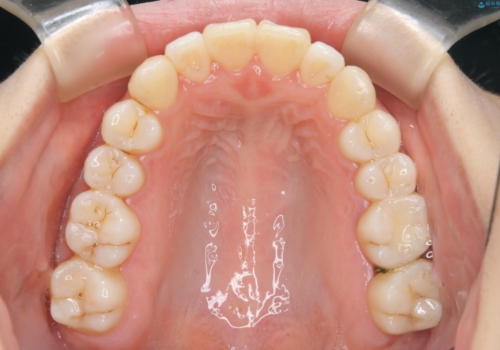

- 矯正装置

- ワイヤー矯正 審美装置

- 治療計画

- 歯のガタつき、顎のズレ、出っ歯を気にして来院された患者様です。

インビザラインの方法でも治せる患者様でしたが、希望によりワイヤー矯正となりました。